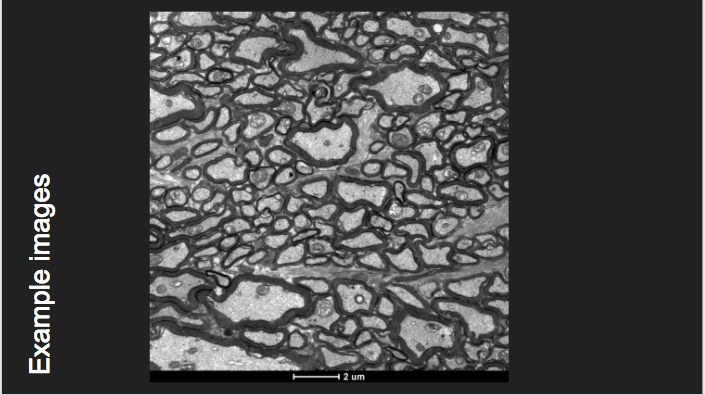

Quantification of cardiac micro-structures on intact whole heart using synchrotron X-ray imaging

Team: Chong Zhang, Patricia Garcia-Canadilla, Hector Dejea, Anne Bonnin, Vedrana Balicevic, Marco Stampanoni, Bart Bijnens, Andrew C. Cook

Example images (adapted for projector viewing -- big fonts, minimal text)